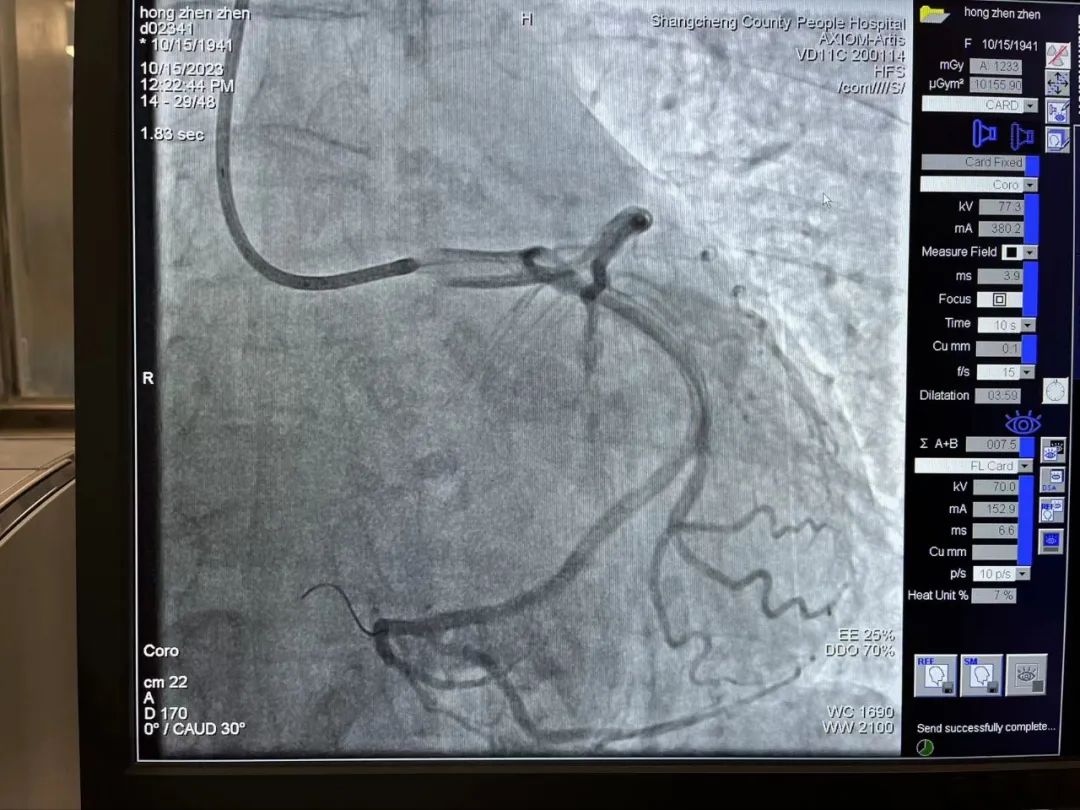

此时,患者的胸痛症状丝毫没有缓解,复查心电图显示下壁导联ST段仍持续抬高。患者病情刻不容缓,经过短暂思考后,熊主任当机立断:尝试开通回旋支远端血管!在熊主任的指导下,刘燃医师小心翼翼的置入预扩球囊扩张回旋支远端,果然发现左旋支直径2.5mm,是右心供血功能血管。但是血管扩张后患者突然出现心率减慢、血压降低的现象,面对这种突发状况,熊主任考虑患者是再灌注后血管痉挛、心律失常,刘医生立即向冠脉内注射硝酸甘油200μg,随后患者心率、血压回升到正常。在进行重复造影后可见患者回旋支远段粗大且长,延伸至右心,再次确定回旋支远端为“罪犯血管”。经过球囊扩张手术后,血管狭窄解除,血流3级,心电图提示下壁导联明显回落,胸痛症状明显缓解,手术有效,抢救成功!

1697763889549360.jpg

1697763915209778.jpg

PTCA术后可见回旋支粗大且长,延伸至右心,给右心供血